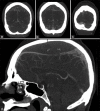

Figure 1

Preoperative noncontrast CT head – (a) coronal cut at the level of the sphenoid sinus, (b) vertex axial cut, (c) mid-sagittal cut, showing a large vertex epidural hematoma with mixed density suggestive of hyperacute hemorrhage, active extravasation and downward herniation. (d) vertex axial cut, bone window, showing coronal suture diastasis